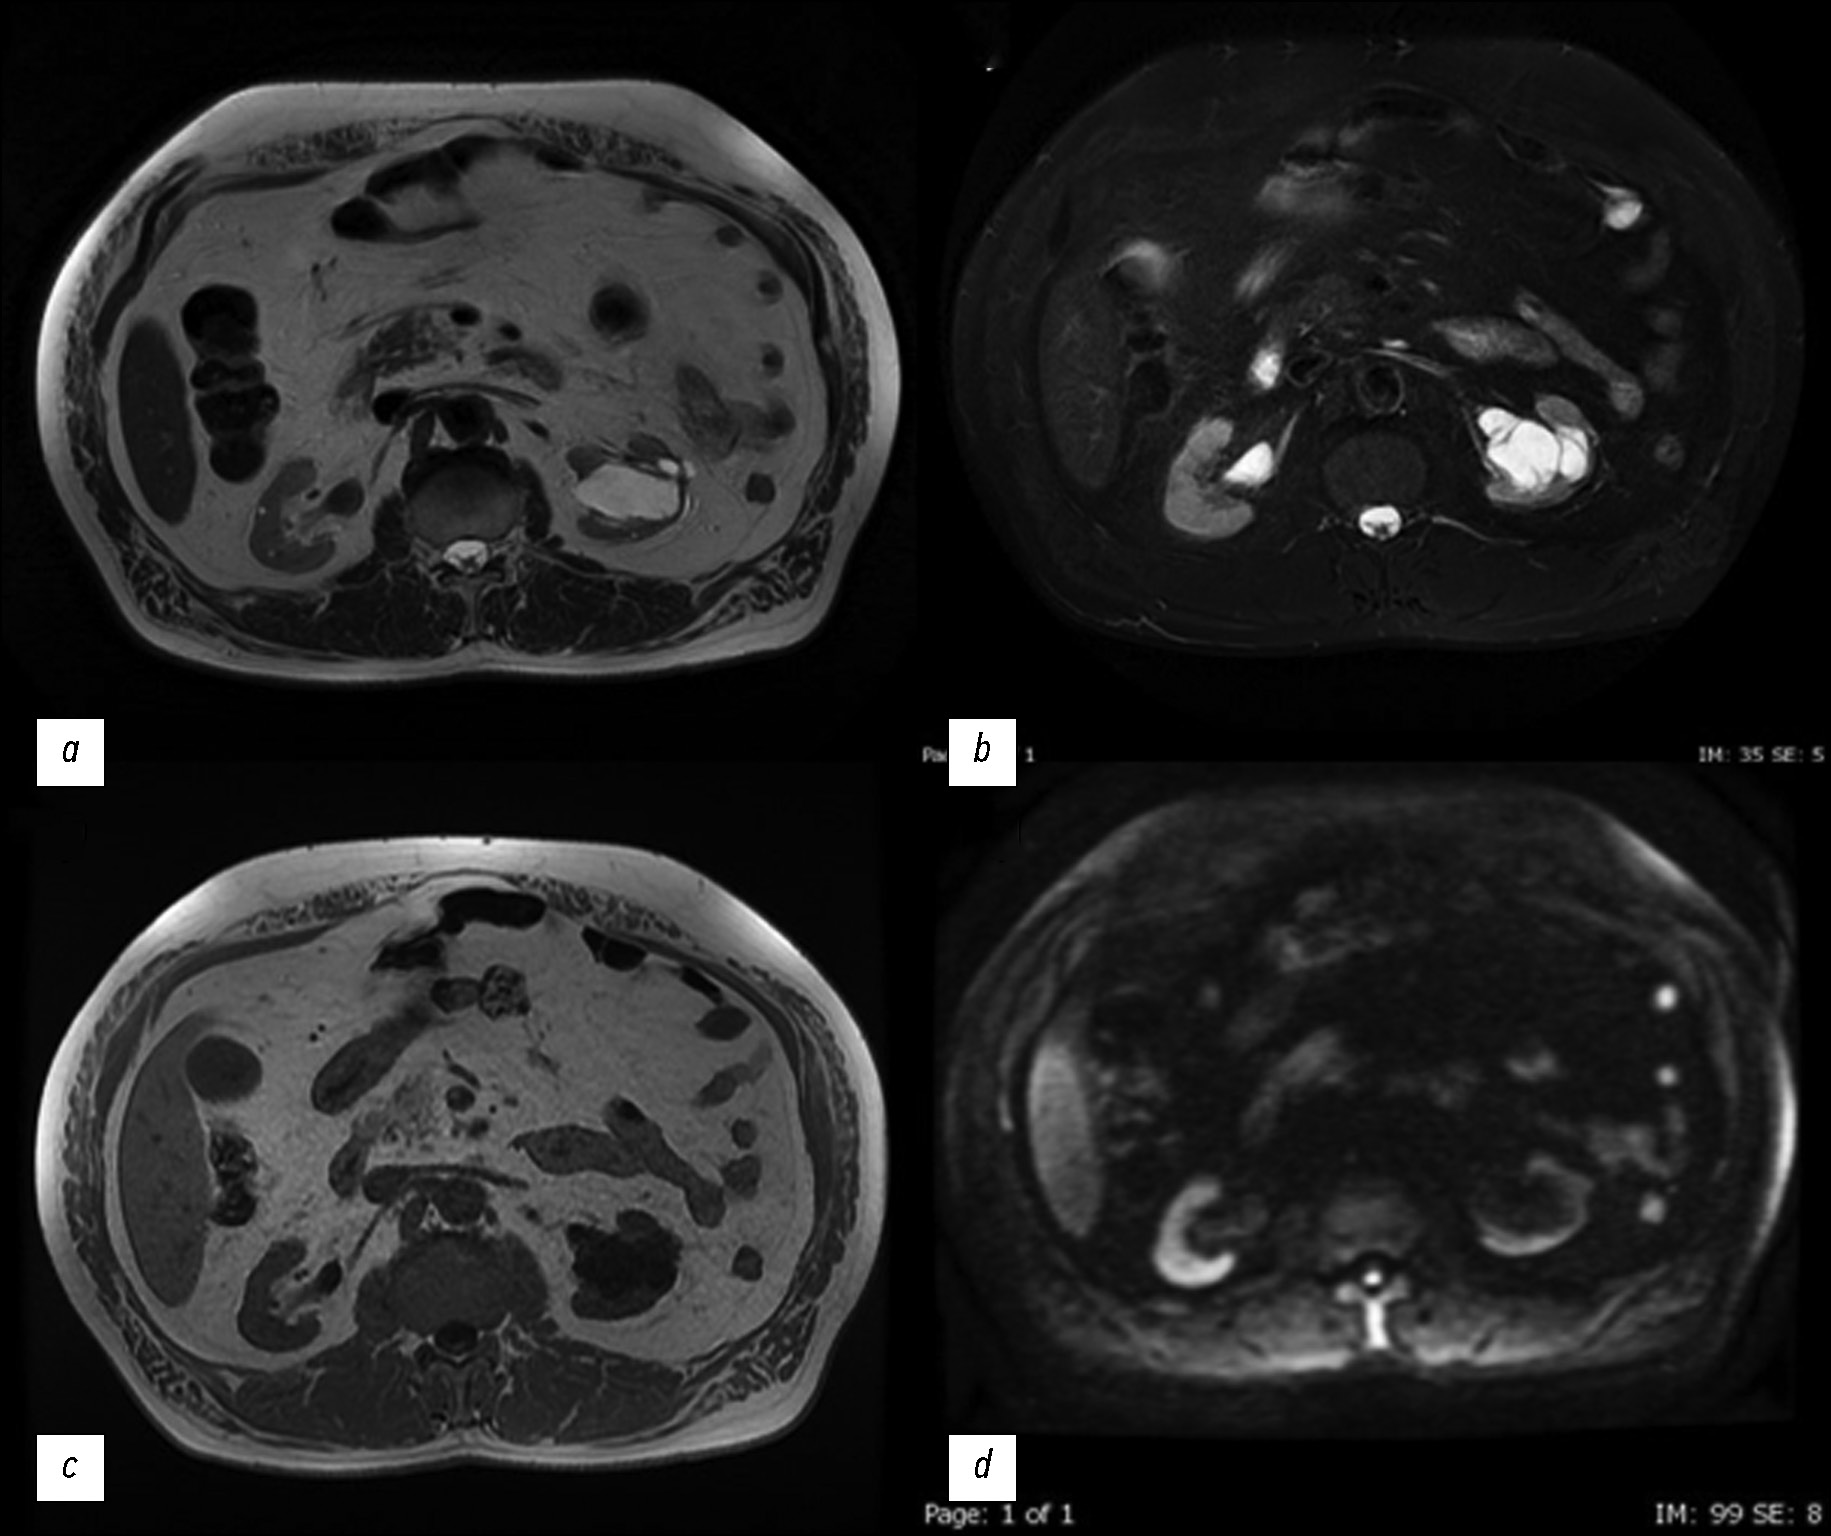

Чтобы более точно охарактеризовать образование и подтвердить гипотезу о наличии дивертикула чашечки почки, которая была выдвинута по результатам КТУ, была проведена магнитно-резонансная урография (МРУ). В средне-нижней части левой почки было обнаружено дольчатое образование, сообщающееся с чашечно-лоханочной системой через узкий канал. В частности, наличие сообщения было подтверждено в экскреторной фазе, когда кистовидная полость заполнилась контрастным веществом. Результаты исследования указывали на наличие дивертикула чашечно-лоханочной системы почки (рис. 4, рис. 5).

Рис. 4. Магнитно-резонансная урография, аксиальные срезы: a — на Т2-взвешенном изображении визуализируется гиперинтенсивное образование; b — на T1-взвешенном изображении в режиме жироподавления после введения контрастного вещества в отсроченной фазе визуализируются гиперинтенсивные образование и почечная лоханка; c — на синфазном изображении образование и выделительная система визуализируются с той же интенсивностью; d — на диффузионно-взвешенном изображении при высоком b-значении ограничение диффузии отсутствует.